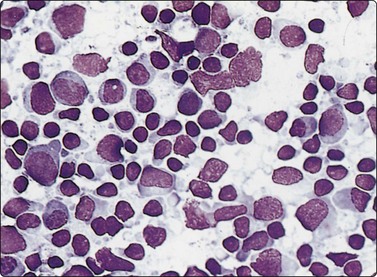

image image

Fig. 5.2 Small cell anaplastic carcinoma

Dispersed malignant cells with dense chromatin, irregular nuclear contour, nuclear molding, inconspicuous nucleoli and cytoplasm; note irregular cytoplasmic (B) and nuclear fragments in the background representing tumor necrosis (A and B) (MGG, HP).